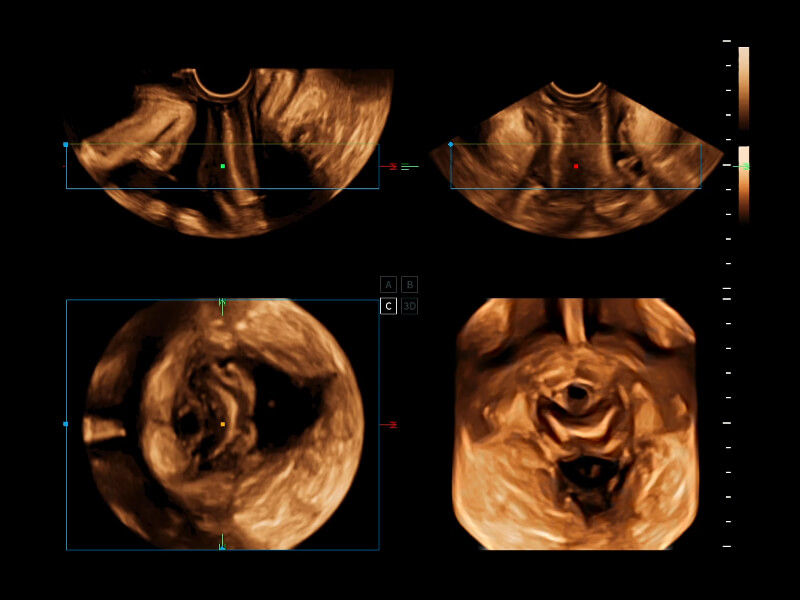

通過(guò)光照模型,使二維血流顯示出立體的效果,增加血流的敏感性、成束性,減少外溢。可以和其他不同的血流技術(shù)聯(lián)合使用,融合不同技術(shù)的優(yōu)勢(shì)。輕松應(yīng)對(duì)微小血管,增強(qiáng)血流的立體效果,提升視覺(jué)敏感性。